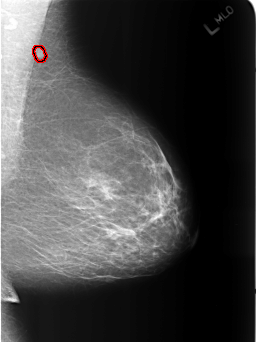

B_3186_1.LEFT_MLO

FILE: B_3186_1.LEFT_MLO.OVERLAY

TOTAL_ABNORMALITIES 1

ABNORMALITY 1

LESION_TYPE MASS SHAPE OVAL-LYMPH_NODE MARGINS CIRCUMSCRIBED

ASSESSMENT 2

SUBTLETY 4

PATHOLOGY BENIGN_WITHOUT_CALLBACK

TOTAL_OUTLINES 1

BOUNDARY